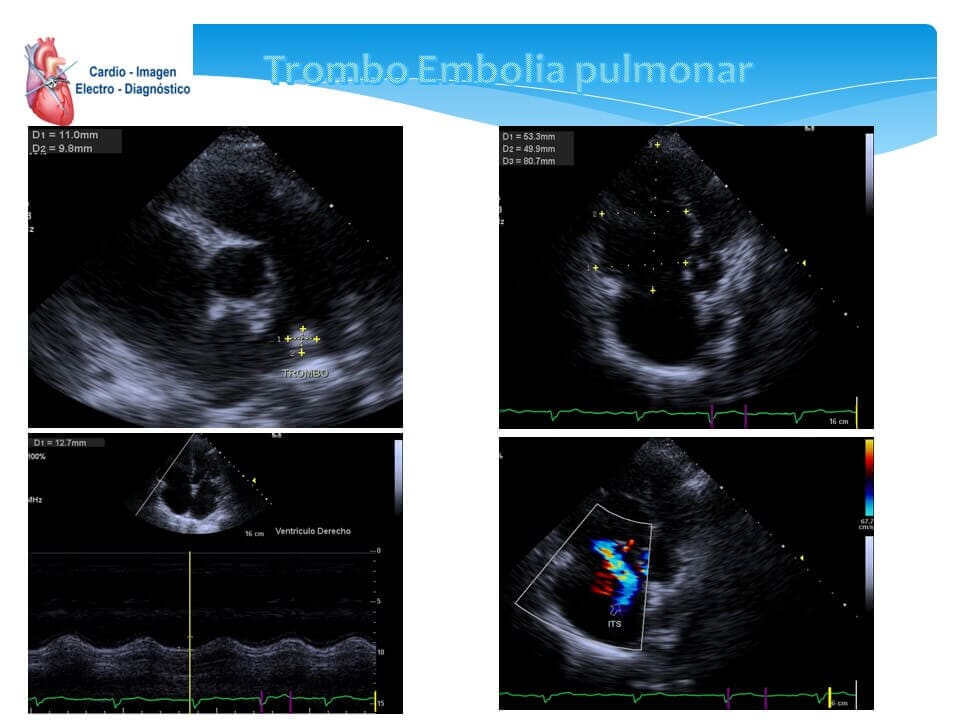

- Ecocardiograma transtorácico

- Ecocardiograma Doppler

- Ecocardiograma bidimensional

- Ecocardiografía